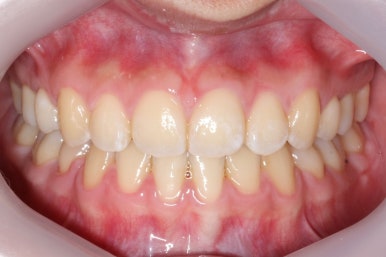

부산교정전문의 키다리아저씨치과에 처음 내원하셨을 때 당시의 입안 모습입니다.

윗니 뿐만 아니라 아랫니 부위에도 덧니가 관찰됩니다. 다른 앞니, 어금니 부위도 약간 삐뚤한 부분이 보입니다.